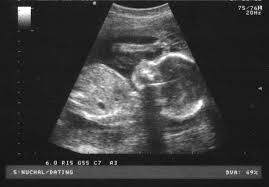

Ultrasound with a Smartphone and a USB Probe

What if you could plug an adapter into your smartphone and use it as an ultrasound machine? Engineers at

Washington University

are working on this thanks to a $100,000 grant provided by

Microsoft

.